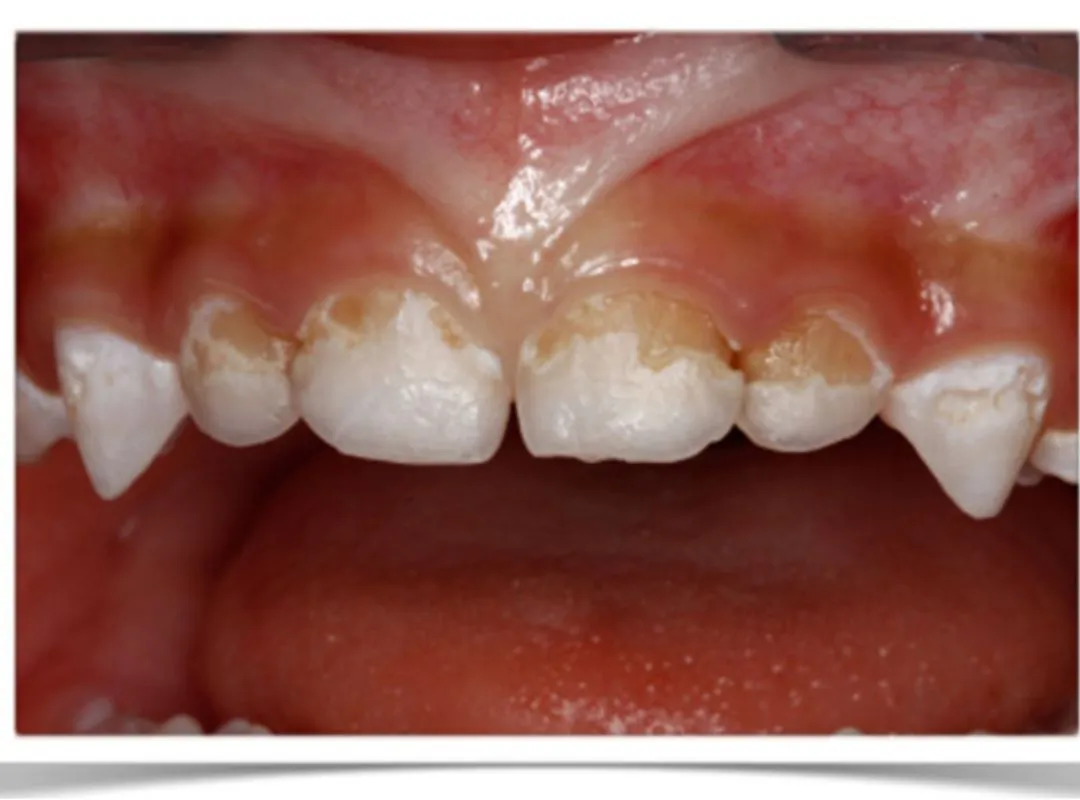

Pediatric Dentistry Gentle, safe, child-friendly care that ensures kids feel safe, comfortable, and confident.

I especially appreciate their expertise in interceptive orthodontics which made a significant difference in my child’s dental development